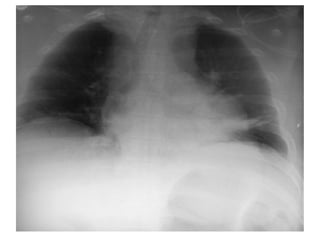

• the most common radiological finding being a

widened mediastinum

• It shouldbe clinically suspected in patients with asymmetry of upper or upper and lower extremity blood pressure, widened pulse pressure and chest wall contusion. • the most common radiological finding being a widened mediastinum